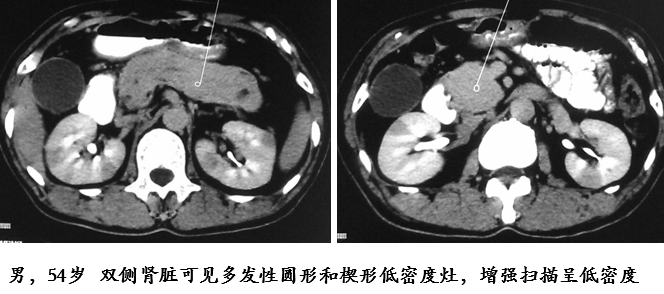

肾脏受累约见于 1/3 的 AIP 患者,为间质性肾炎。双肾多发病灶,CT 表现为皮质内小圆形、楔形、不规则形低密度灶,肾盂可受累,增强扫描动脉期呈低密度,延迟期呈轻度强化MRI:T1WI 等或低信号,T2WI 低信号,DWI 高信号,增强扫描轻度强化

b795954cc9ae9b8dceaf5bfcadaf0bba.png

2000fa07286e64a85a60908e4156f137.jpg